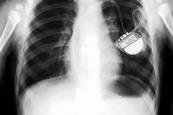

Hospitals must update 100,000 pacemakers after safety fault

Hospitals are having to update more than 100,000 patients’ pacemakers – and replace hundreds of the devices – after the manufacturer discovered their batteries run down years early, HSJ has learned.